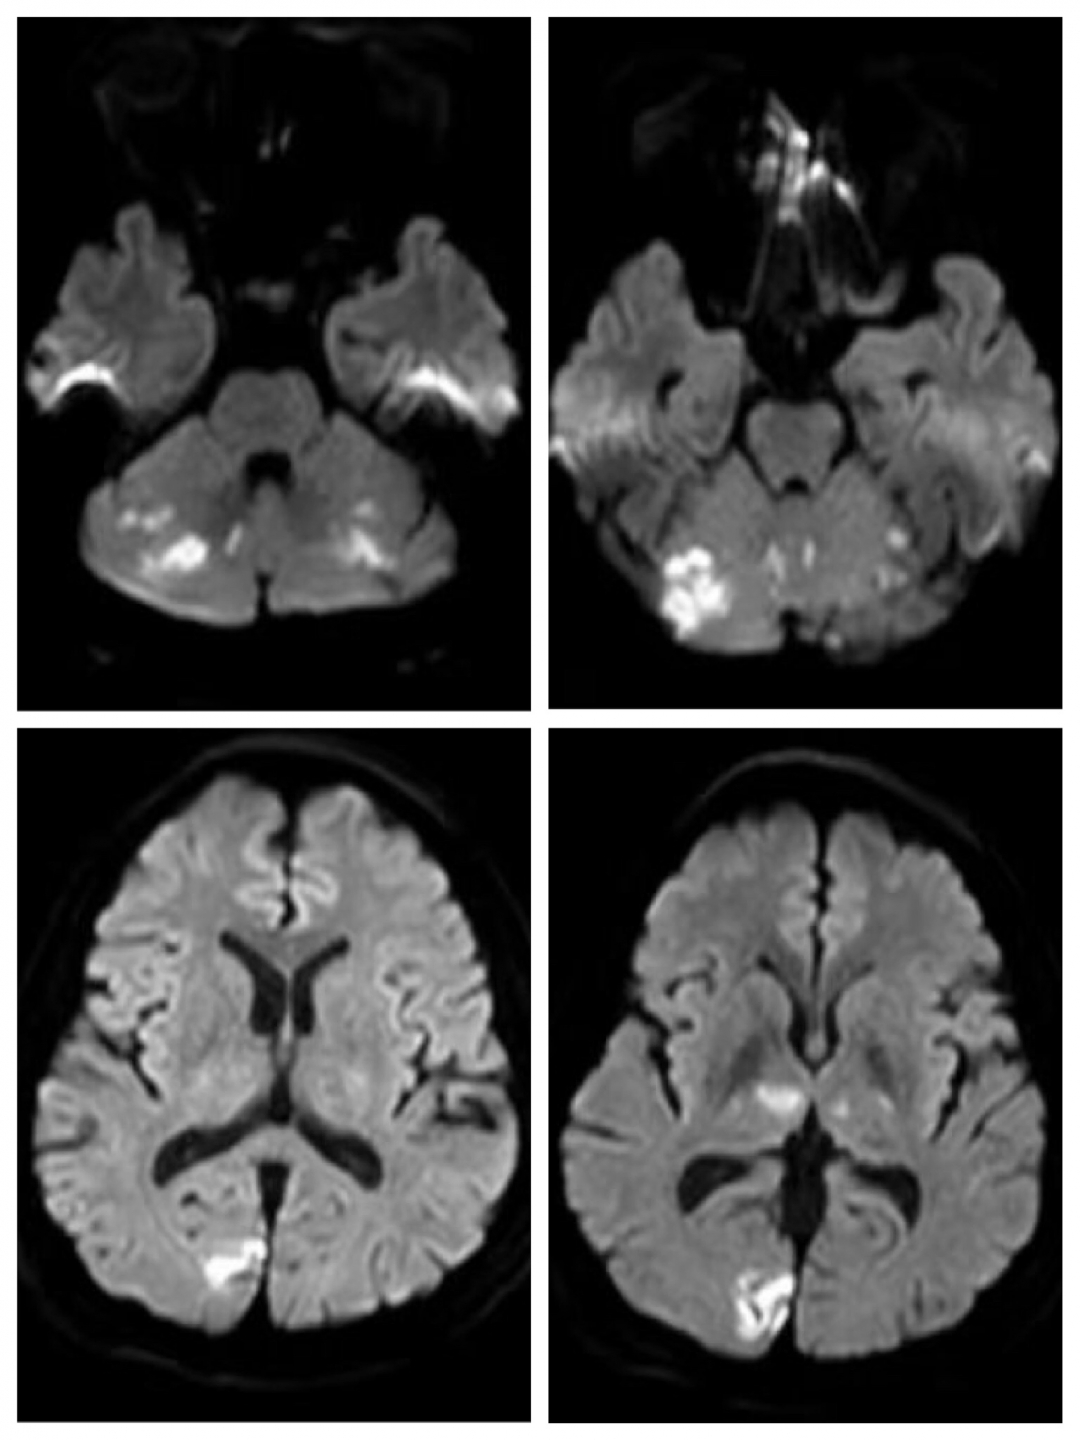

当日轮值我院卒中中心急诊溶栓班的神经内二科主治医师贾磊华即刻到位,通过仔细询问病史,查体后初步诊断为后循环梗死。随即开启卒中中心绿色通道,紧急为患者安排头颅核磁及磁共振血管成像检查,结果可见双侧小脑、颞枕叶、丘脑多发梗死,确诊为急性后循环梗死——基底动脉尖综合征。

(溶栓前患者头颅磁共振成像及磁敏感加权成像)